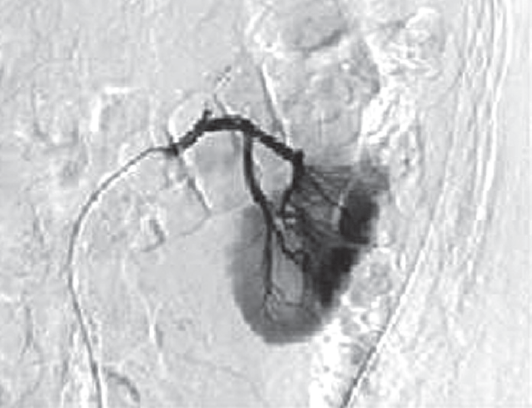

На 2-е сутки послеоперационного периода зафиксировано поступление по дренажу геморрагического отделяемого в объеме 400 мл. Пациенту экстренно выполнена ангиография левой почечной артерии. Выявлена экстравазация контрастного вещества через культю верхней сегментарной артерии почки (рис. 4). Осуществлена селективная эмболизация верхней сегментарной артерии (рис. 5). После эмболизации наблюдалось постепенное уменьшение отделяемого по дренажу до 30 мл. На 7-е сутки после операции отмечено поступление по дренажу около 500 мл светло-желтого отделяемого, при биохимическом анализе которого содержание мочевины составило 12,8 ммоль/л, креатинина 488 ммоль/л, что указывало на формирование мочевого свища. Пациенту выполнены цистоскопия и ретроградная уретеропиелография. Выявлена экстравазация контрастного вещества через верхнюю группу чашечек. Произведено стентирование левого мочеточника двухпетлевым антирефлюксным мочеточниковым стентом Колопласт Fr 6, после чего выделение мочи по дренажу прекратилось. Дренажная трубка из забрюшинного пространства удалена на 9-е сутки после операции, и еще через 2 дня пациент выписан из стационара в удовлетворительном состоянии. Мочеточниковый стент удален через 4 недели после его установки.

Рис. 5. Контрольная ангиография после суперселективной эмболизации верхней сегментарной артерии. Экстравазации контрастного вещества нет

Fig. 5. Control angiography after superselective embolization of the superior segmental artery. There is no extravasation of the contrast agent